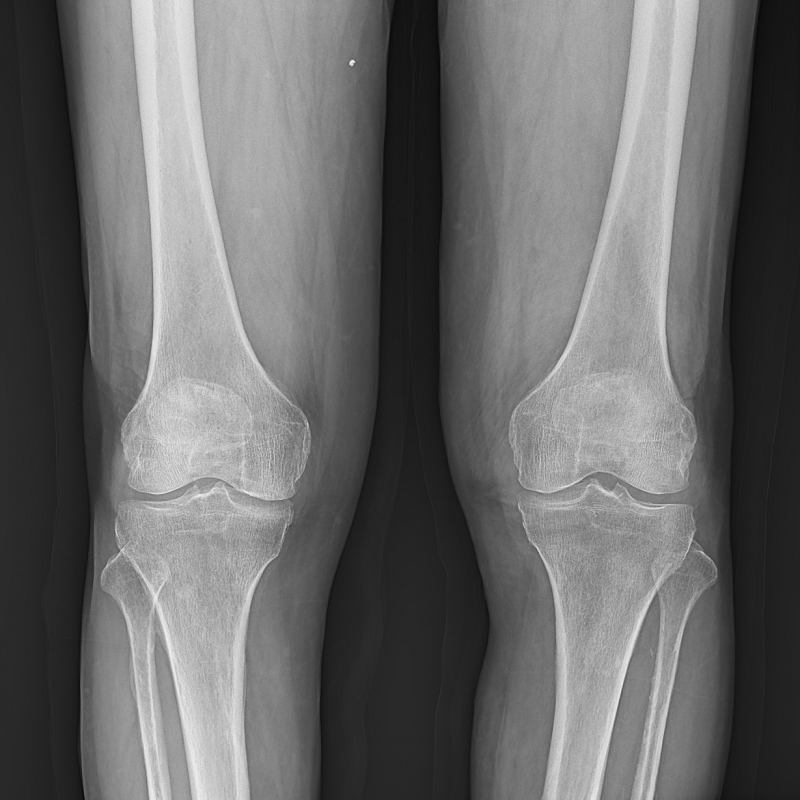

●呈現全下肢或全脊柱圖像

●在脊柱及下肢畸形矯正手術治療中,為術前方案制定和術后復查提供精準測量

●有效解決傳統X光片不能一次成像問題,為患者提供更加優質的醫療服務